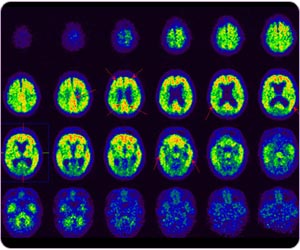

Dementia

C-11 PIB PET detects typical Alzheimer's disease with amyloid plaque at post cingulate gyrus, frontal lobe, precuneus, parietal lobe and temporal lobe.

Region-based quantitative analysis for C-11 PIB brain study